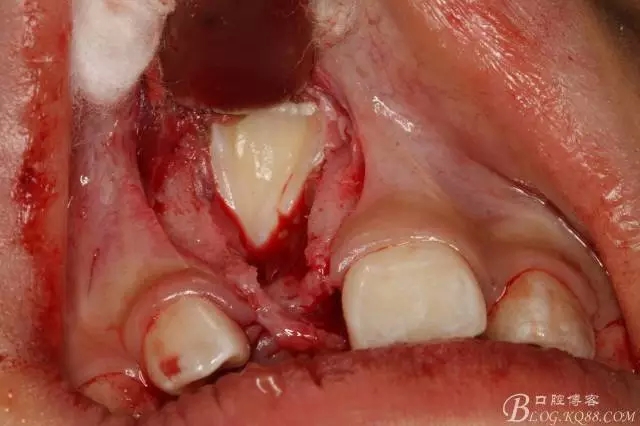

圖4.局部浸潤麻醉,左側(cè)21正常,11可在前庭溝處捫及隆起

圖5.先做腭側(cè)齦溝內(nèi)水平切口,翻瓣。